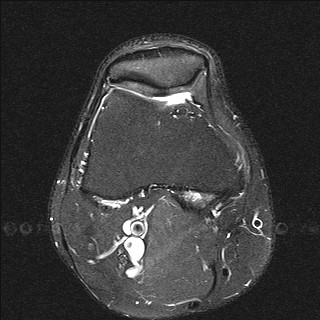

МРТ коленного сустава

Особая диагностическая ценность МРТ коленного сустава состоит в получении исчерпывающей картины дегенеративно-дистрофических изменений (хронические артриты и остеоартрозы, повреждения суставных поверхностей) и возможности визуализации самых мелких травм (разрывы связок, сухожилий, переломы), визуализация хряща с последующим его картированием для определения дистрофических и травматических изменений.

Дистрофические изменения суставного хряща надколенника (с использованием опции «картирования хряща»)

МРТ помогает с большой точностью установить полный или же частичный разрыв мениска, прекрасно и наглядно отображает состояние связок коленного сустава. При диагностировании передней крестообразной связки МРТ показывает разрывы ясно и четко в 96%. Магнитно-резонансная томография наглядно демонстрирует не только разрывы сухожилий, но и гораздо более тонкие проблемы, возникающие во внутренней структуре, сопряженные с воспалением или рубцеванием тканей, которые при неблагоприятном прогнозе могут вызвать определенные хронические заболевания.